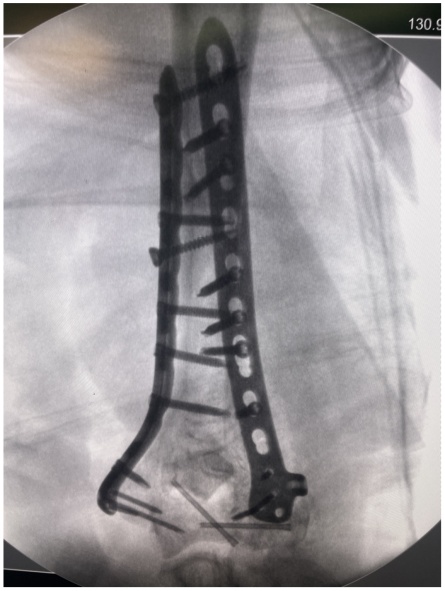

待麻醉生效后,患者取左侧卧位于手术台上,右上肢术区常规消毒,铺无菌单,贴皮肤保护膜。取右上臂中远段后正中入路,纵行切开一长约18.0 cm手术切口,依次切开皮肤、皮下,切开筋膜层,充分显露尺骨鹰嘴,将尺神经分离充分显露后予以保护,应用微型摆锯“V”形截骨尺骨鹰嘴,将尺骨鹰嘴连同肱三头肌腱剥离,湿盐水纱布保护,注意保护桡神经,暴露肱骨中远段,见肱骨中下段螺旋形骨折,分离短缩移位,肱骨滑车、肱骨小头、肱骨内外髁多处骨折线,分离旋转移位,局部骨质缺损,将肱骨中下段、肱骨滑车、肱骨小头、肱骨内外髁骨折复位,克氏针临时固定,后分别于右肱骨远折端内侧、后侧铺放2枚解剖型钢板,注意保护桡神经和尺神经,拧入数枚螺钉固定,C臂透视见钢板及螺钉长度及位置满意(见图2)。并于外髁骨缺损处植入3.0 g β-磷酸钙生物陶瓷不规则颗粒。将截断的尺骨鹰嘴复位后打入两根克氏针临时固定,并应用钢丝“8”字捆绑固定(见图3),活动肘关节,见骨折复位固定确实,关节无异响和绞索。后将尺神经松解前置,见神经松紧带适宜。后清点器械、纱布无误后,冲洗术区,彻底止血,术区留置负压引流管1枚,撒入盐酸万古霉素0.5 g及止血粉于切口内,预防感染及促进止血,应用可吸收性倒刺线2根逐层缝合肌层及皮下,一次性使用皮肤缝合器关闭切口,无菌敷料进行外包扎,石膏托固定肘关节于功能位(90˚屈曲),术毕。手术经过顺利,麻醉效果满意,术中出血量约1200 ml,给予输注ABO血型AB型Rh(D)阳性去白细胞悬浮红细胞2单位,过程中无明显输血不良反应,术后患者呈清醒状态安返病房。

Figure 2. Intraoperative findings and C-arm fluoroscopy with anteroposterior and lateral radiographs

2. 术中外相及C型臂透视正侧位X线片